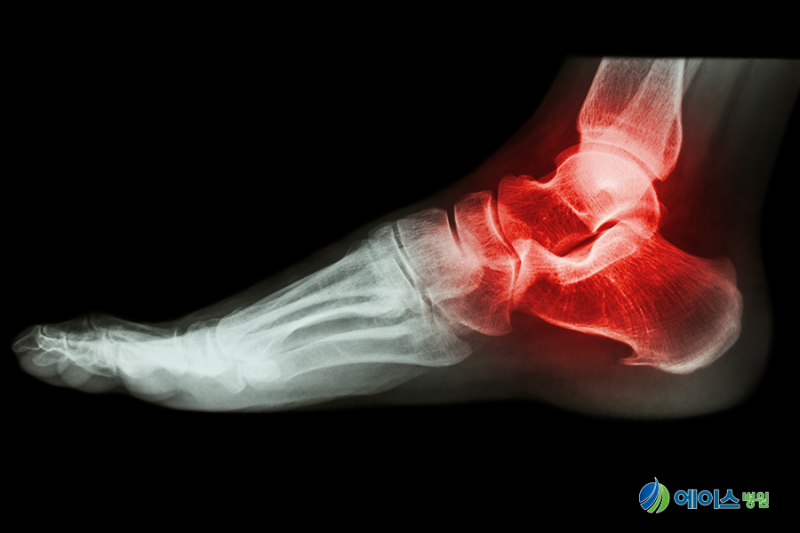

“나는 발목이 고정될 것이라고 들었는데, 인공 관절 수술보다는 인공 관절 수술보다 더 많은 것들이 있다”고 인공 관절 수술을 받고 있다.발목 관절염이 있는 환자 3분의 3분의 3분의 1은 인공 관절 수술을 받고 있다.반면, 발 클리닉 관절 수술을 하는 미국에서는 인공지능 관절 수술을 받고 최근 국내보다 적극적으로 수행되고 발목 인공 관절 수술을 받고 있다.#크리 인공 관절 수술을 하는 이유는 왜 더 고정됩니까?

발목 인공 관절 수술을 수행하는 데 어려움을 겪고 있기 때문이다.우선, 발목 인공 관절 장비 자체는 다른 공동 장비 자체가 부족해서 인공 관절 부위에 비해 인공지능 관절이 덜 관심이 적고 생산되지 않기 때문이다.

미국, 유럽 등 발목 인공 관절 수술을 하는 회사들은 인공 관절 수술에서 비교적 활발하지만, 인공 관절 수술을 하지 않는다.또한 국내 발목 인공지능을 만드는 것이 좋을 것 같아. 하지만 수요가 높지 않다고 생각합니다.또한 발목에 비해 상대적으로 적은 수의 발목이 있고 다른 관절에 비해 인공 관절에 비해 조작하기가 어렵다.발목 인공 관절 수술은 시간이 걸리므로 인공 관절 수술을 받을 수 있기 때문에 인공 관절 수술을 받을 수 있는 병원이 거의 없다.나는 한국에서 정보를 공유하고 데이터를 축적하고 데이터를 축적하고 데이터를 축적하는 것이 필요하다고 생각한다.